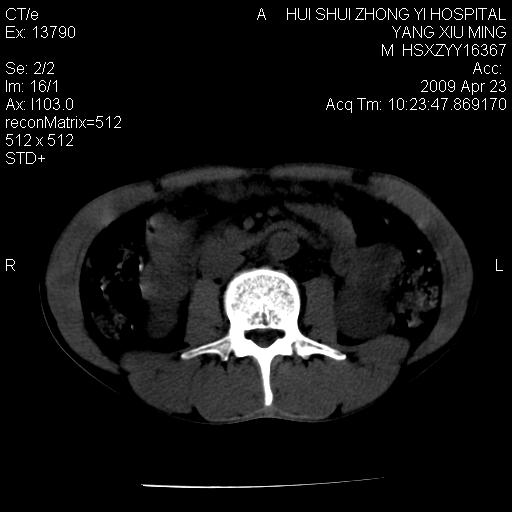

腹膜后淋巴结增大,转移、淋巴瘤?胰腺增大,胰腺炎?占位?颈部考虑增大淋巴结。建议腹部增强扫描。

缺少强化资料,暂考虑胰腺癌广泛转移.

连最基本的ct值都没有测        腹部的窗宽窗位太大了     影响诊断

黑!广泛淋巴结肿大不符合胰腺癌转移。胰腺周围淋巴结肿大致使胰腺看起来大。考虑淋巴瘤可能大。